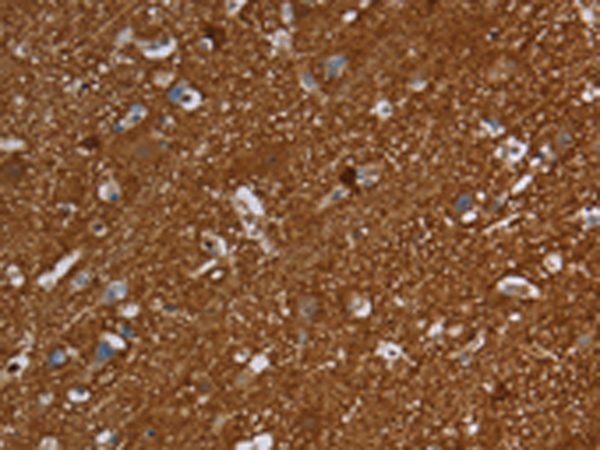

分类: 科研抗体货号: P00099别名: SR; BCSG1应用: WB,IHC反应种属: Human